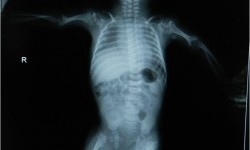

Dysplasia Epiphysealis Punctata

Fig 1: Infantogram